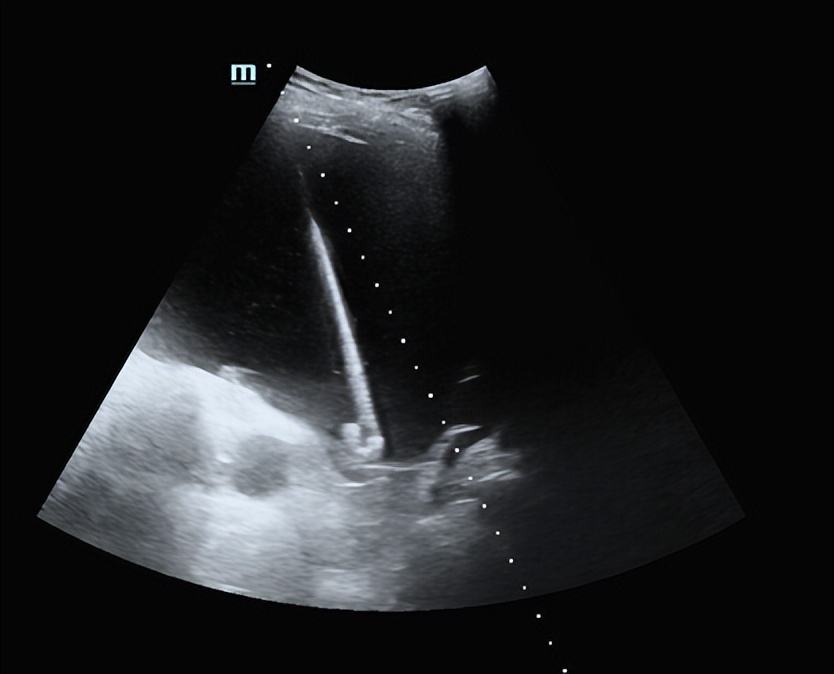

首先对最大的囊肿进行置管引流。超声确定最佳穿刺路径,消毒铺巾,上穿刺架,调整引导线,18G PTC针进入囊肿中心,置入导丝,扩皮,置入猪尾管持续引流,返回病房。

PTC针穿刺囊肿

导丝置入囊肿

猪尾巴管置入囊肿